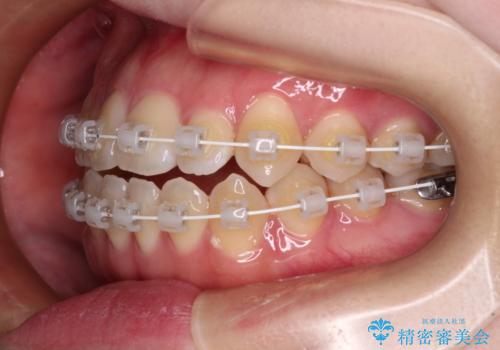

舌突出癖による開咬 舌のトレーニングを行いながら前歯の隙間を改善

- 上下前歯の隙間を気にして来院された患者様です。

前歯が、舌の突出癖により上下前歯が非接触となっている状態でした。

上下前歯が非接触である開咬は、インビザラインによる治療がお勧めではありますが、しっかりと使う自信がないとのことで、ワイヤー装置にて治療を行うこととしました。

ワイヤー矯正での開咬改善には時間がかかります。

舌の突出癖改善のトレーニングをしっかりと行っていただき、上下前歯が接触する咬み合わせを達成することができました。